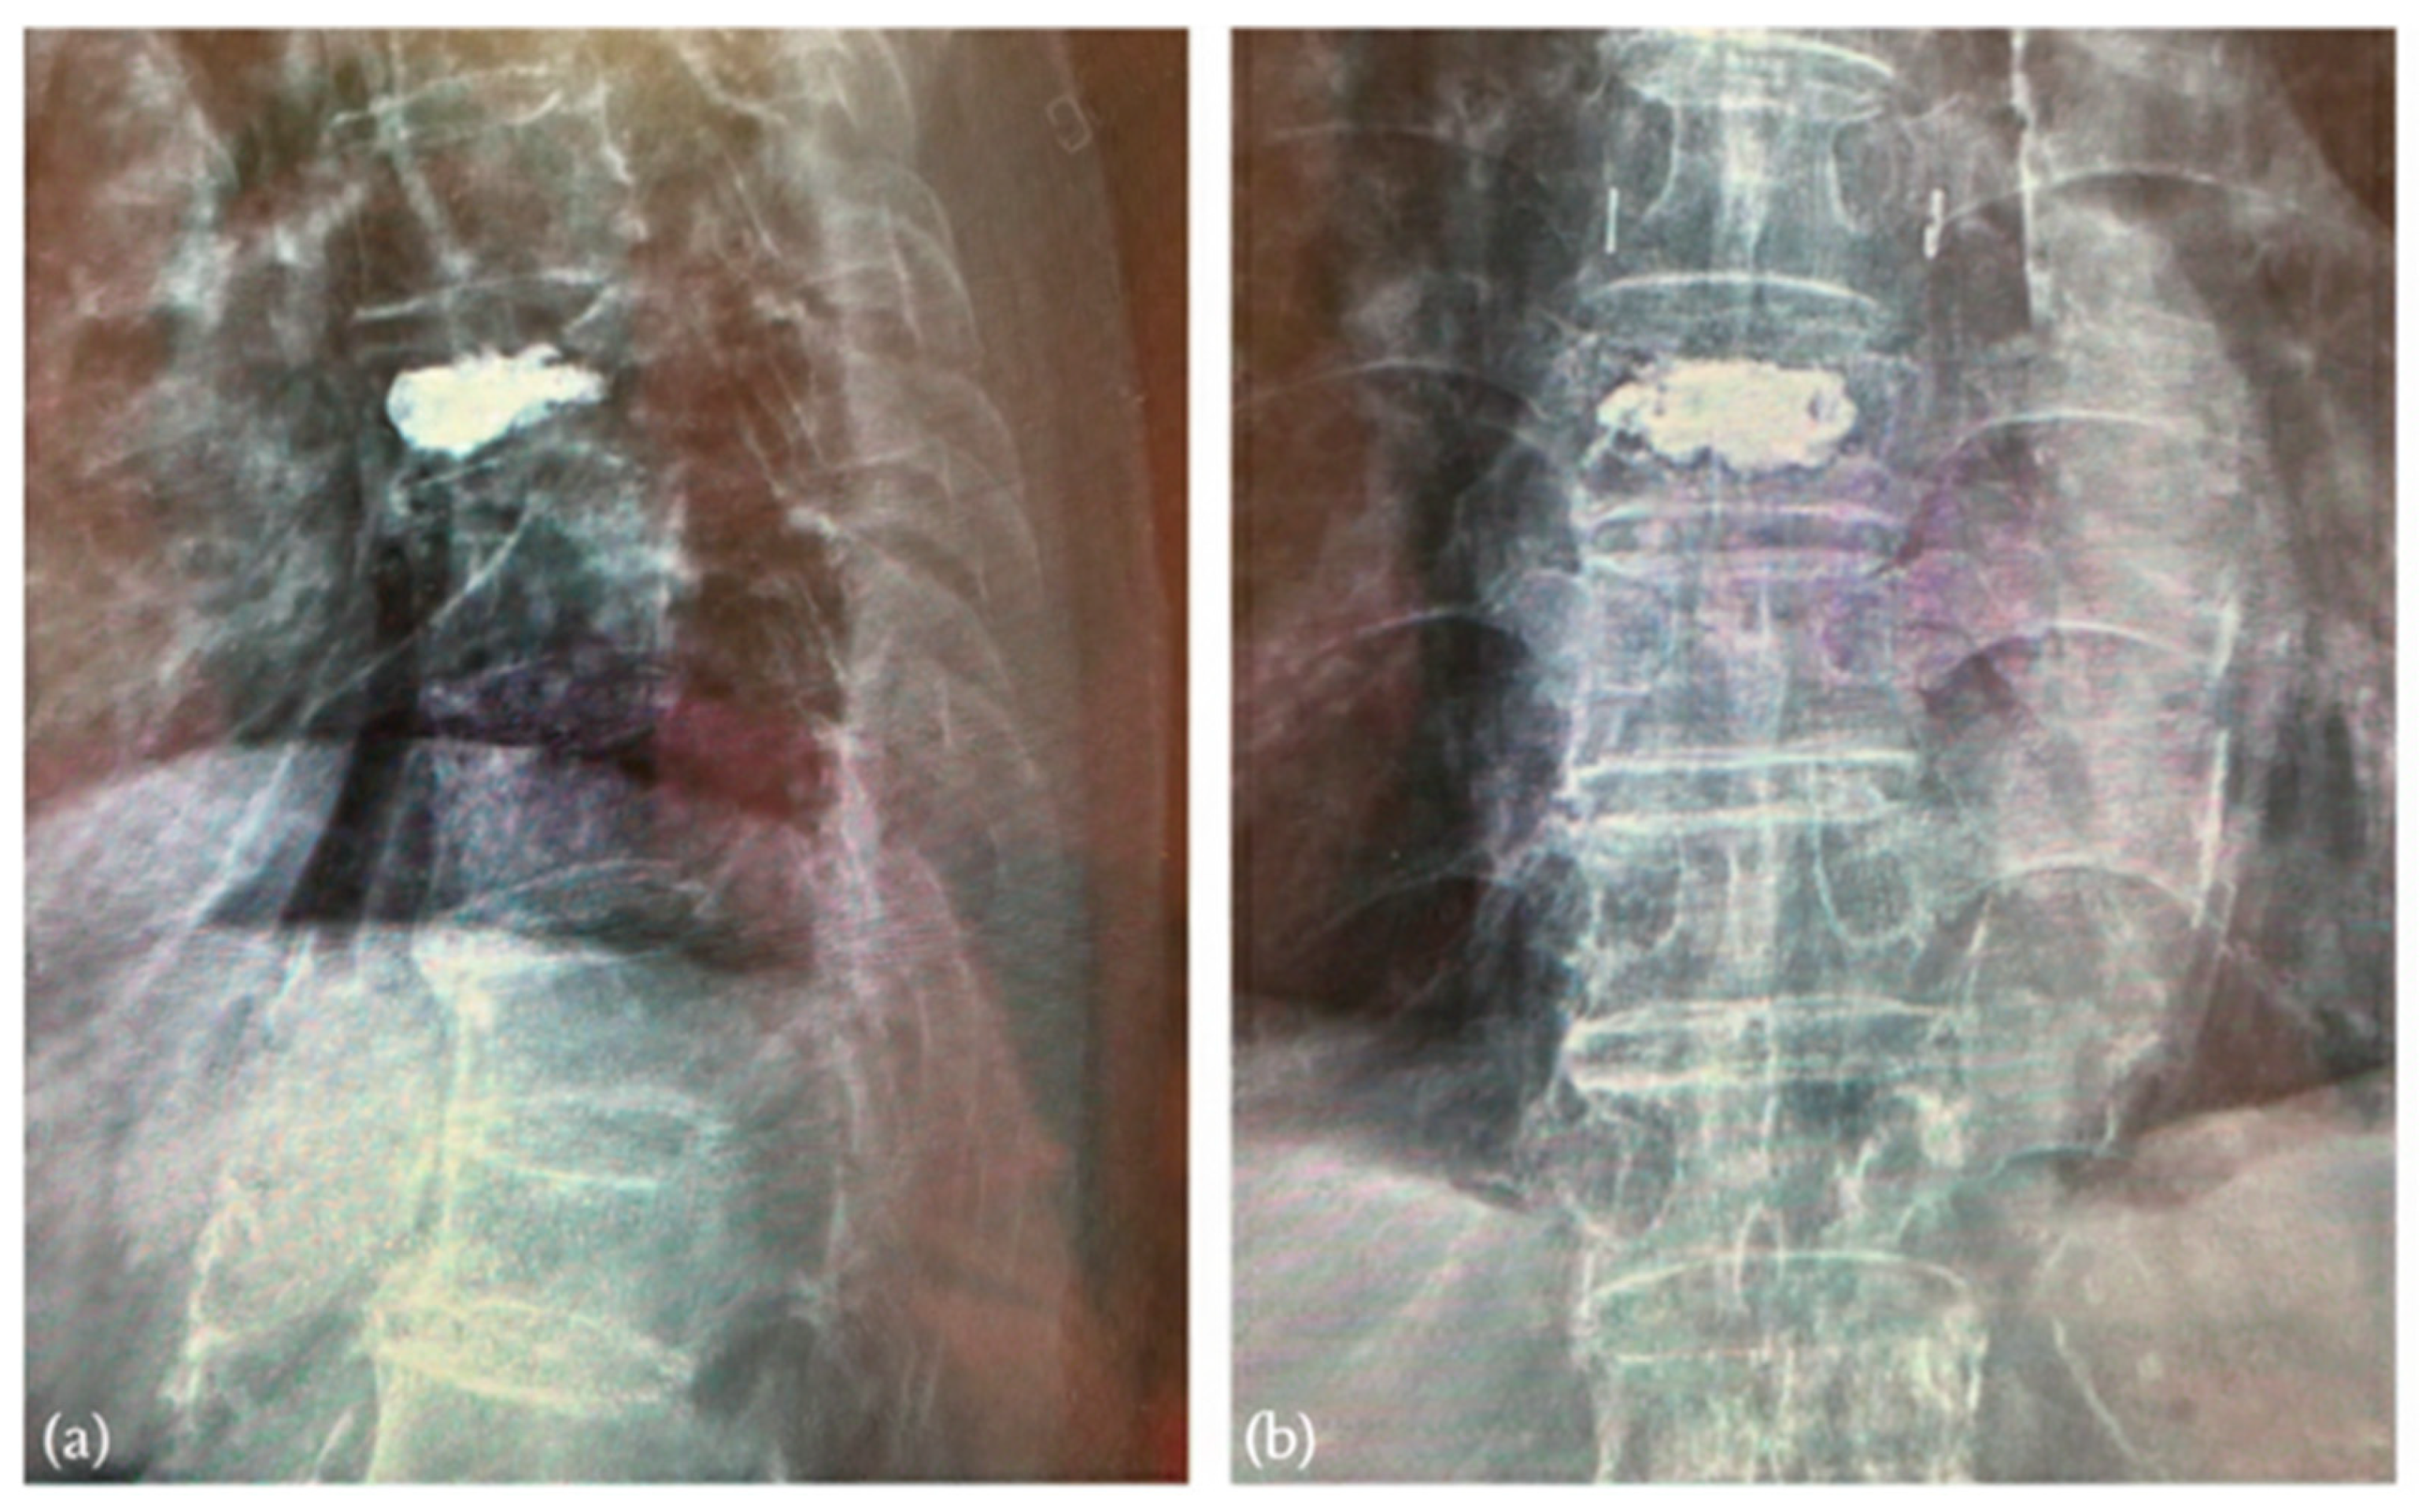

3.1. Surveillance of Cement Leakage

3.2. Decompression Maneuver

3.3. Postoperative Clinical and Radiographic Outcomes